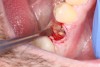

3. Make sure the socket is bleeding (Figure 6). If necessary, decorticate the remaining socket walls, using a round bur or surgical-type bur, to create a bleeding wound that will facilitate early vascularization and the beginning of the primary healing cascade.

Fig 6.The socket must be bleeding before delivering the graft material. This facilitates the healing cascade and greatly increases the success of the socket preservation.

Figure 6